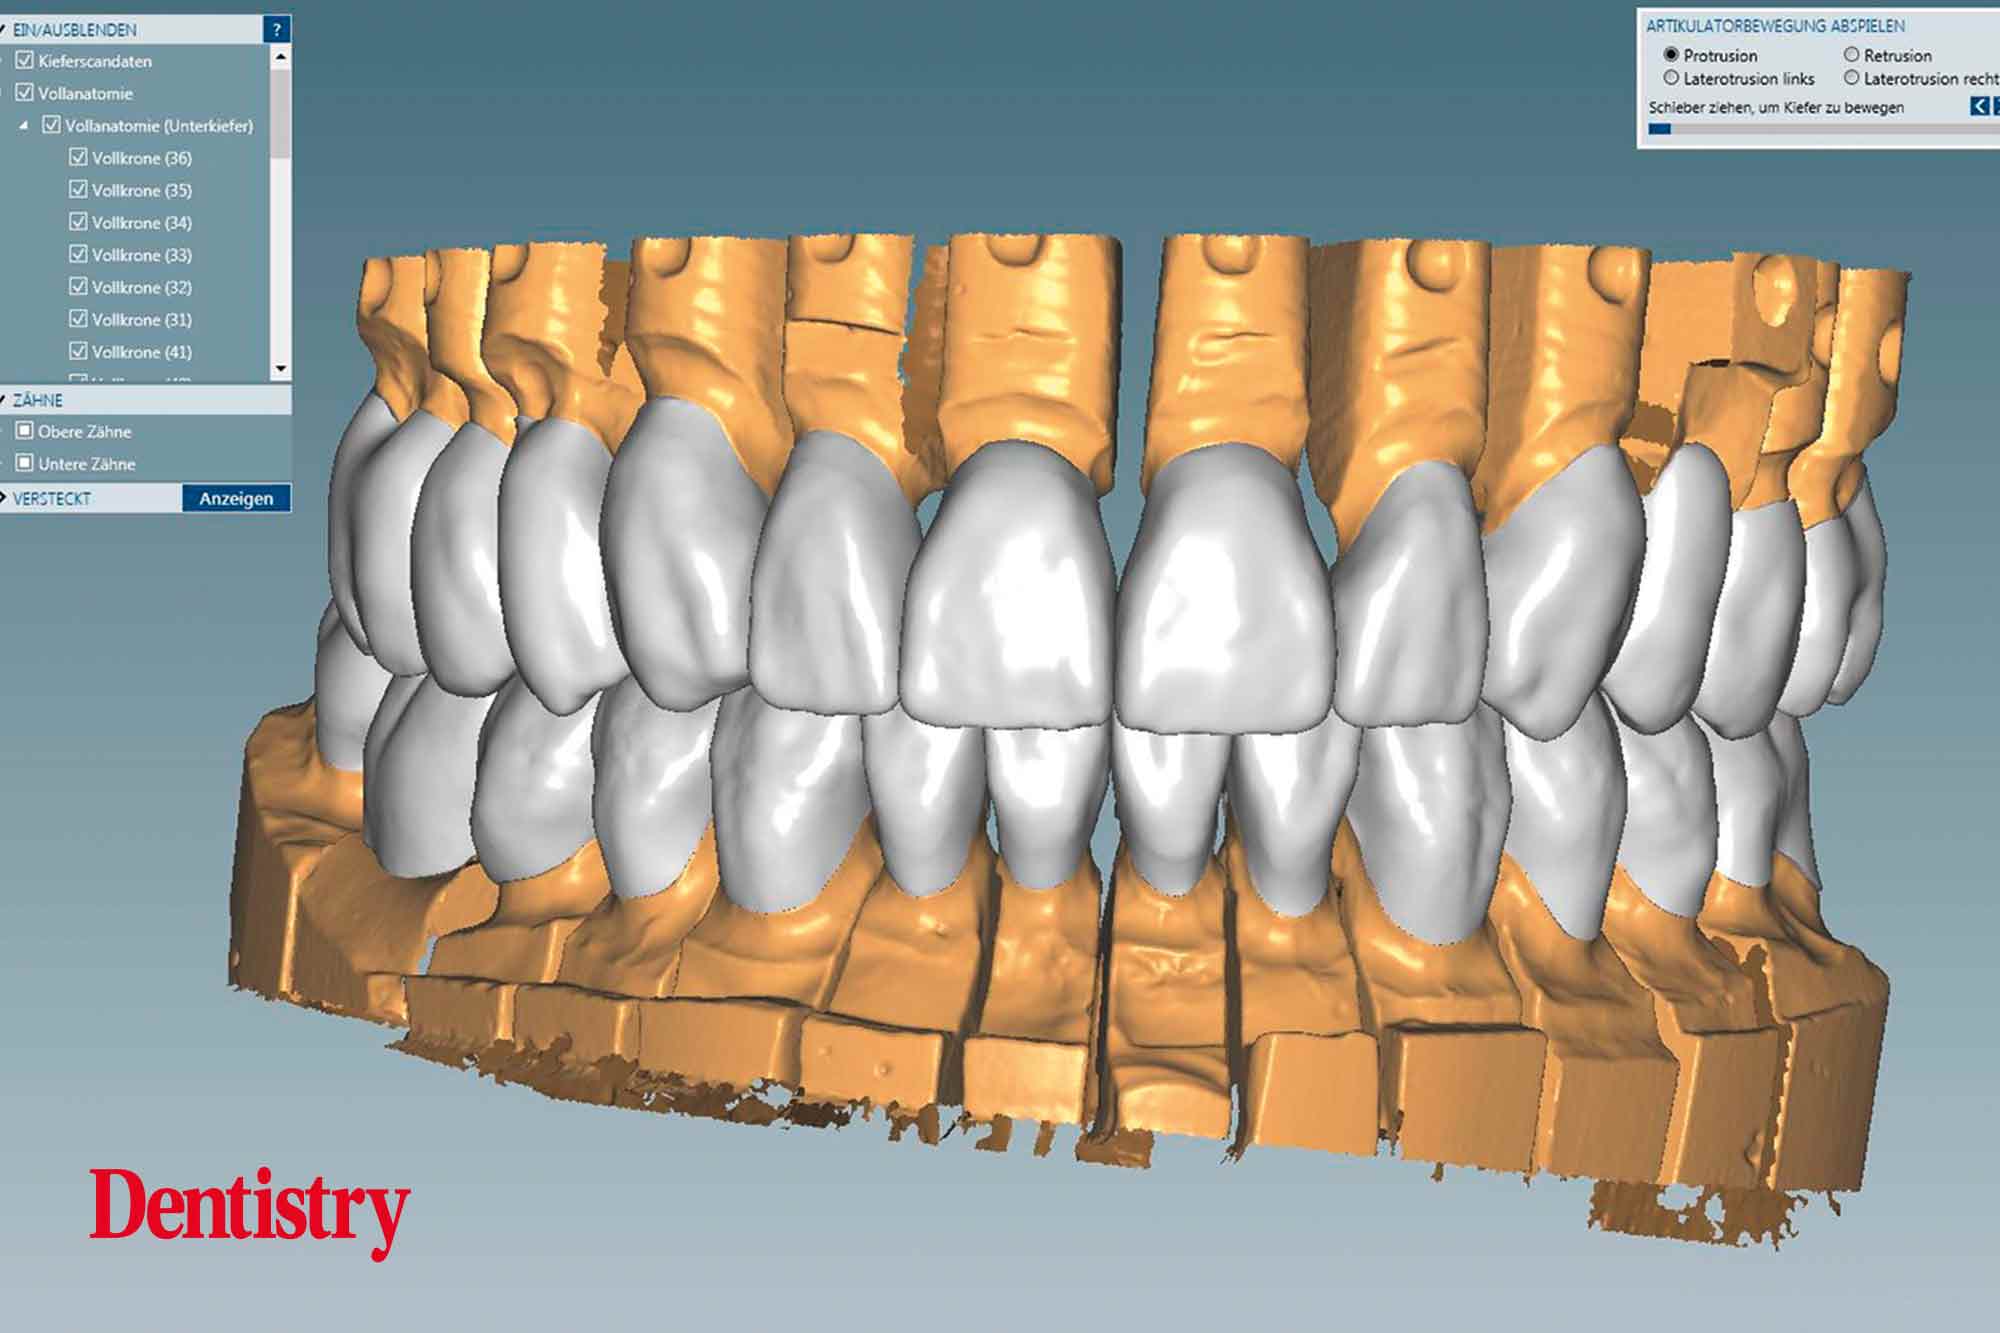

The scanned models were evaluated on a virtual 11 articulator. Temporary Ceramill PMMA (Amann Girrbach) transparent acrylic crowns were CAD planned (Figures 3a to 3d).

All patient parameters including condylar inclination were transferred to the Ceramill Artex articulator and the lateral and protrusive excursions were established while having no contact with the anterior teeth (Figures 5 to 8).

The virtual temporary crowns were 3D printed and then temporarily cemented. This test phase with temporary crowns is a mandatory step because after the patient evaluated the temporary crowns for several weeks, corrections were made with the input of the patient, thus reducing the risk of errors in the subsequent final crowns.